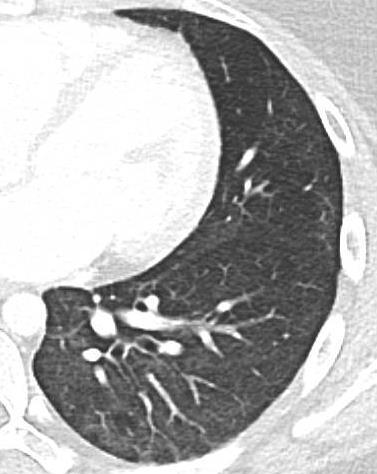

Acute Pediatric COVID-19: CT

21 Imaging of Covid 19 infection in children

3 Phases

Early: "Halo" sign

Local infection

Progressive: Diffuse GGO

Developed: Consolidation

Surr vasc congestion

Inflammation - adj alveoli

Alveoli fill with fluid/cells

CT

• Bilateral & multifocal GGO, +/Consolidations or both

• Halo sign

• Peripheral and subpleural